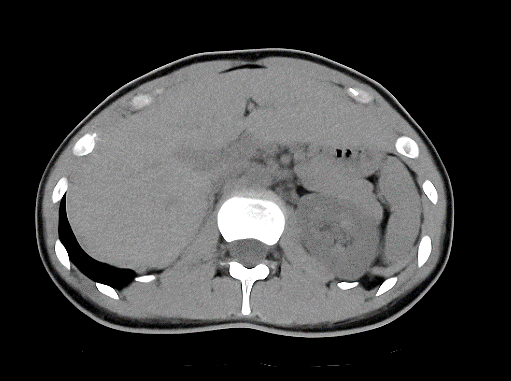

CT検査

当院では、Canon製Aquilion Prime SP 80列を使用しています。短時間で広範囲の撮影ができる他に、撮影したデータを元に任意の角度に合わせた断面像を生成したり、骨や臓器を3次元的に表示して観察することができます。また当院では3D医用画像処理ワークステーション(ZIO・VINCENT)を導入しており、より詳細な3次元画像の作成を行っています。